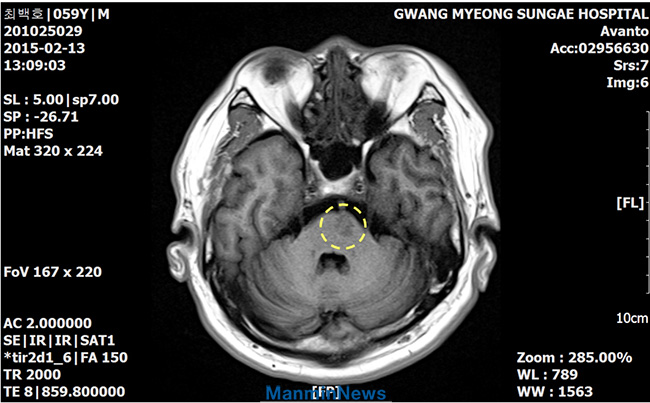

Доктор сказал, что это был церебральный инфаркт, то есть инсульт, и направил меня в отделение интенсивной помощи. Симптомы болезни усугублялись, и правую сторону моего тела полностью парализовало. Я не мог даже пошевелить пальцем. Я не мог сам ни сесть, ни встать.

До молитвы – инфаркт в левом мосту головного мозга

После молитвы – стабильно